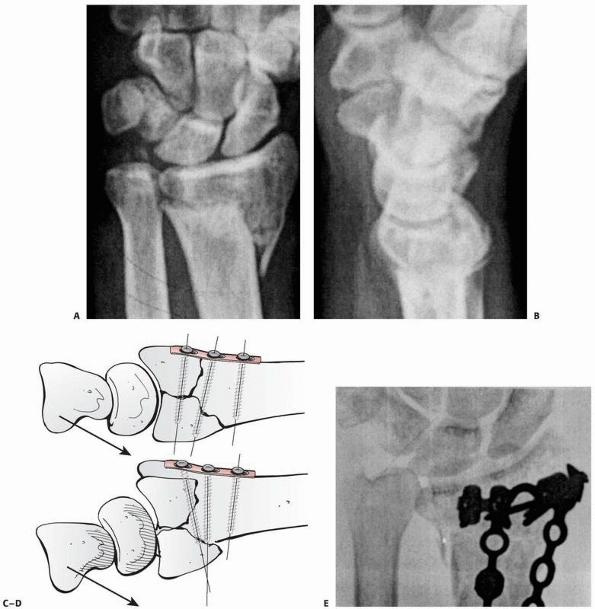

![]() |

FIGURE 30-8

The cross-sectional anatomy of the radius with comminution dorsally and radially. Note the tendency to dorsal collapse is the result of dorsal comminution and the collapse at the midcarpal joint. |

FIGURE 30-11 A. Disruption of the critical corner of the radius results in depression of the lunate facet. B-E. The radiographic and clinical effects are demonstrated.

|